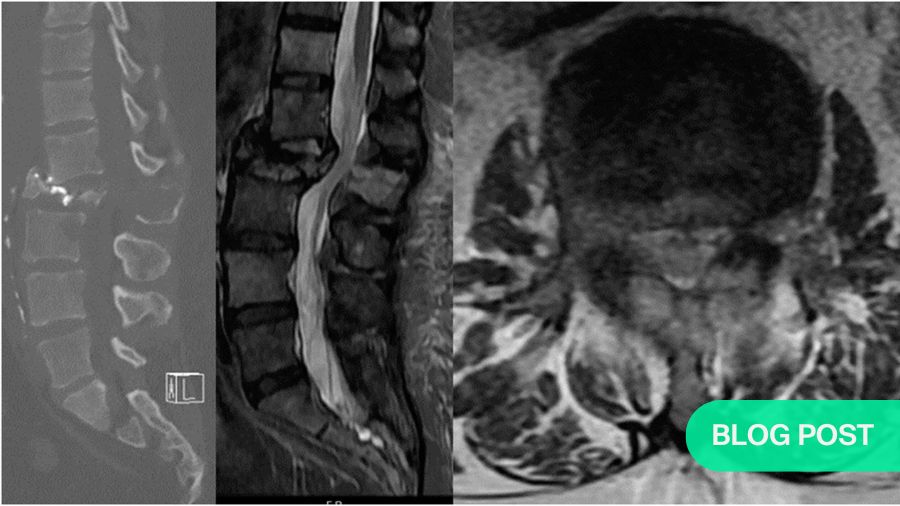

Case 1: A 46-year-old man presents with 3 months of weight loss, back pain, and cough. He is a non-smoker.

Chest imaging reveals a lung nodule consistent with NSCLC (adenocarcinoma) and molecular analysis reveals an EGFR mutation. There is a single metastatic lesion at L2 causing a pathologic fracture with greater than 50% loss of height and retropulsion. He is ambulatory and has pain-limited weakness 4/5 on the hip flexor. He has good performance status (ECOG 1) and his Spine Instability Neoplastic Score is 17. Given the recent diagnosis of NSCLC and the favorable EGFR mutation, patient is started on osimertinib and offered separation surgery plus stabilization.